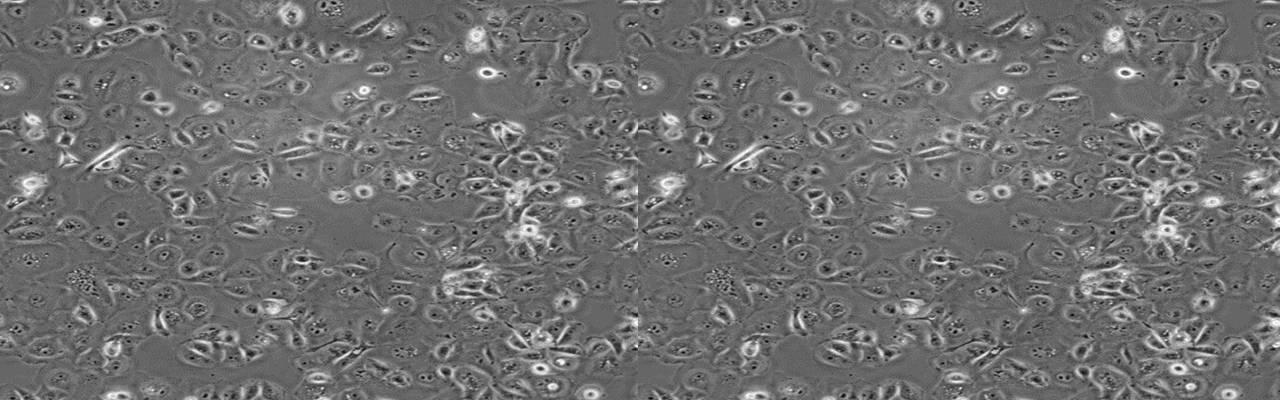

| 名称 | BEL/FU |

| 细胞全名 | 人肝癌氟尿嘧啶耐药株 |

| 生长特性: | 贴壁生长 |